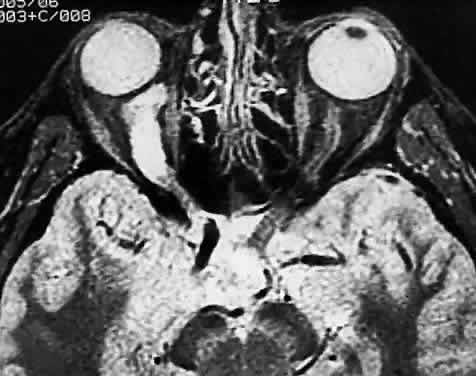

Modern imaging techniques have greatly facilitated the evaluation of optic nerve sheath meningioma and glioma.29 Plain orbital radiographs occasionally show abnormalities of the optic foramen and calcification. Imaging studies (CT and MRI) show diffuse tubular or less commonly, globular enlargement of the nerve sheath complex (Fig. 43).49,50 As with its intracranial counterpart, the optic nerve meningioma typically enhances brightly. “Tram-tracking” results when the thickened sheath outlines the uninvolved central nerve from which it is sharply demarcated. Although characteristic of optic nerve meningioma, this is not specific and can be seen in inflammatory conditions and rarely even in optic nerve glioma. Precise localization of the extent of the tumor is determined with MRI studies, particularly with fat-saturation techniques. Dilation of the anterior perioptic space (perioptic cyst) between the anterior edge of the tumor and the globe is seen in instances in which the tumor does not encroach on the globe and is a distinct and common feature.51,52

Fig. 43. Primary meningioma of right optic nerve. Computed tomography.